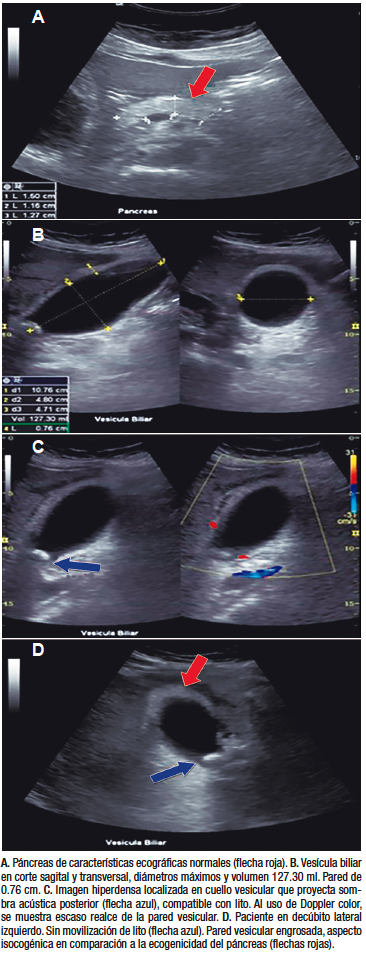

Se solicitó un ultrasonido de hígado, vesícula biliar y páncreas, el cual evidenció una imagen hiperecoica en fondo de la vesícula biliar compatible con lito, engrosamiento de la pared y signo de Murphy ecográfico positivo, compatible con colecistitis crónica agudizada más hidrocolecisto por volumen vesicular de 127,30 cc (Figura 1).

Figura 1. Ultrasonido en escala de grises, con transductor convexo

En retrospectiva, analizando las imágenes del ultrasonido, se piensa que pudo haber una relación entre la ecogenicidad de la pared vesicular y la ecogenicidad en el páncreas, ya que notamos que ambos segmentos tenían similitudes ecográficas, coincidiendo con el nódulo descripto por patología; sin embargo, al ser una entidad poco frecuente, aun en manos experimentadas puede pasar desapercibido en el área de imagen.